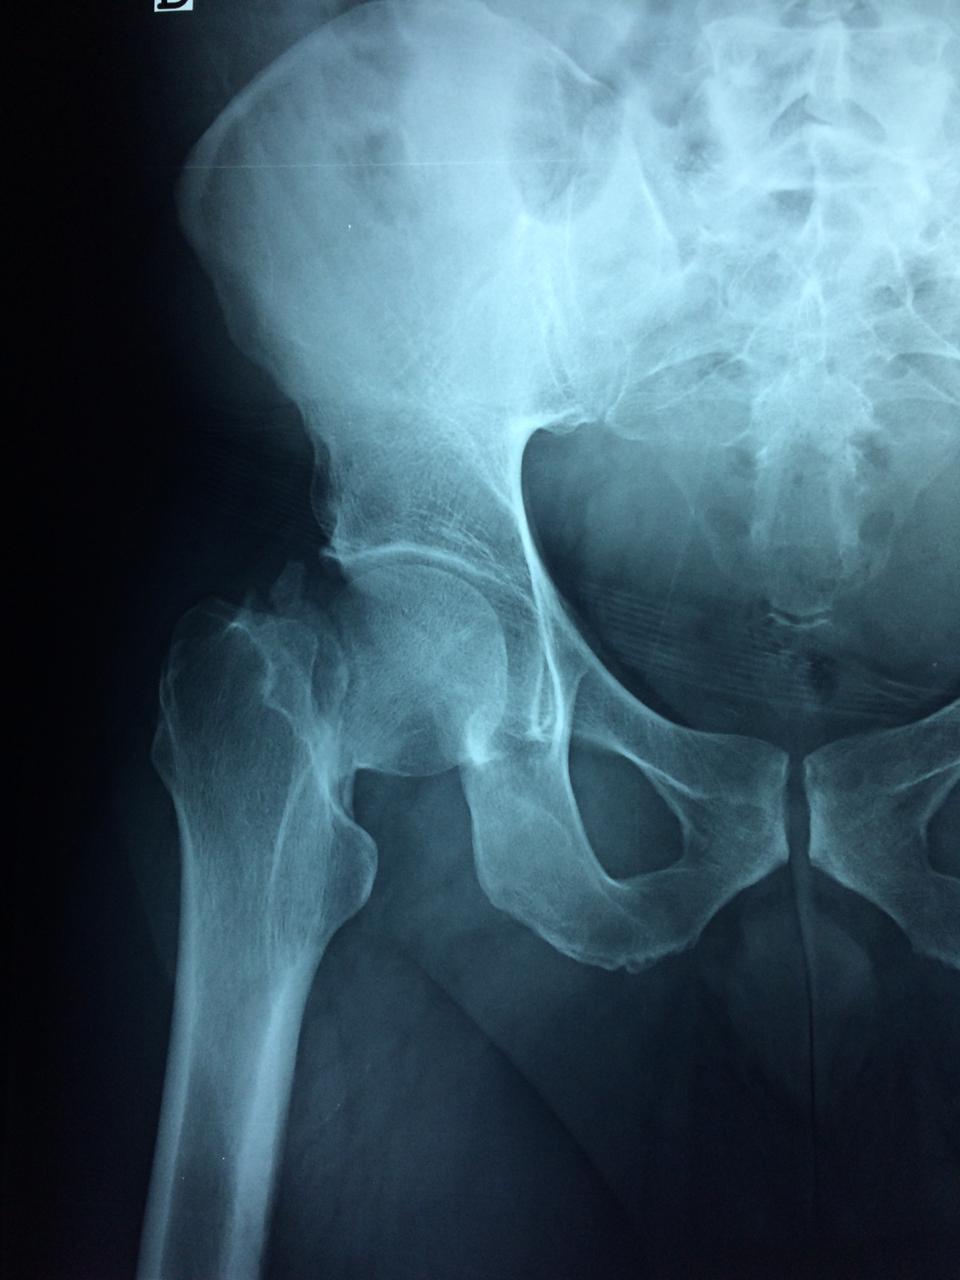

La cirugía de fractura de cadera se realiza para reparar una ruptura en la parte superior del hueso del muslo. Este hueso se denomina fémur.

Es parte de la articulación coxofemoral. Si una fractura de cadera no recibe tratamiento, es posible que deba permanecer en una silla o en la cama.

Esto puede llevar a otros problemas de salud potencialmente mortales, sobre todo si usted es una persona mayor.

A menudo se recomienda la cirugía para reparar la fractura debido a dichos riesgos.